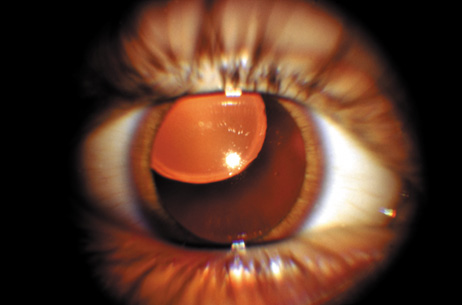

The dense bilateral lens opacities may present as a biconvex-shaped cataract or as posterior, polar, nuclear, or total cataract. The discoid lens shape may result from loss of lens material due to a posterior lens capsule defect4 or defective lens fiber formation and subsequent degeneration.5 The cataracts are present at birth, and glaucoma may be present congenitally or develop within the first 3 years of life. Other ocular findings may include corneal opacity, mitotic pupil, enophthalmos, and hypotonia.6 The cognitive impairment presents with a discrete behavioral phenotype that includes temper tantrums, irritability, complex repetitive behaviors, and unusual mannerisms. Severe renal Fanconi's syndrome may lead to progressive renal impairment. Most boys will develop a distinctive facies and habitus, and attain a height of less than 5 feet because of developmental retardation. Female carriers manifest characteristic but usually asymptomatic lenticular opacities that will correctly identify carrier status with 100% sensitivity in postpubertal females. These opacities are typically small, irregularly shaped, off-white or gray in color, nonrefractile in appearance, and distributed around the lens equator, more anteriorly than posteriorly (Figs. 1 and 2). Most importantly, and distinctively, these opacities are clustered in radial bands or wedges in the peripheral cortex of the lens and are visible by retroillumination. Typically, the opacities are moderately dense for one or two clock-hours, are then less numerous or even absent for another clock-hour or two, and so on. These opacities must be differentiated from the polychromatic, iridescent “crystals” found in Steinert's myotonic dystrophy (DM), gray-white random opacities in carriers of X-linked adrenoleukodystrophy, sutural opacities in Nance-Horan's (NH) syndrome, snowflake granules beneath the anterior and posterior capsule in diabetes mellitus, highly uniform white dots of hypoparathyroidism, and equatorial opacities in cataracta coronaria or ceruleana. Some females also manifest a dense white, central, posterior cortical cataract in the precapsular area. Although the posterior central cataract is apparently congenital, the equatorial and anterior cortical punctate opacities are uncommon in prepubertal female Lowe's syndrome carriers.7 Carrier status may also be confirmed by DNA diagnosis.

Fig. 2. OCRL. Retroillumination of small, irregularly shaped, nonrefractile anterior cortical opacities in the lens of a female carrier of OCRL. (Courtesy of Dr. R.A. Lewis, Baylor College, Houston, Texas.)